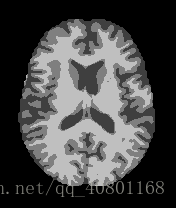

以上三张图片是成年人的大脑核磁共振图像,从左至右分别表示正常人、轻微某病、严重某病。

现在我在用深度学习(BP神经网络、CNN卷积神经网络、迁移学习等)在研究如何分类。